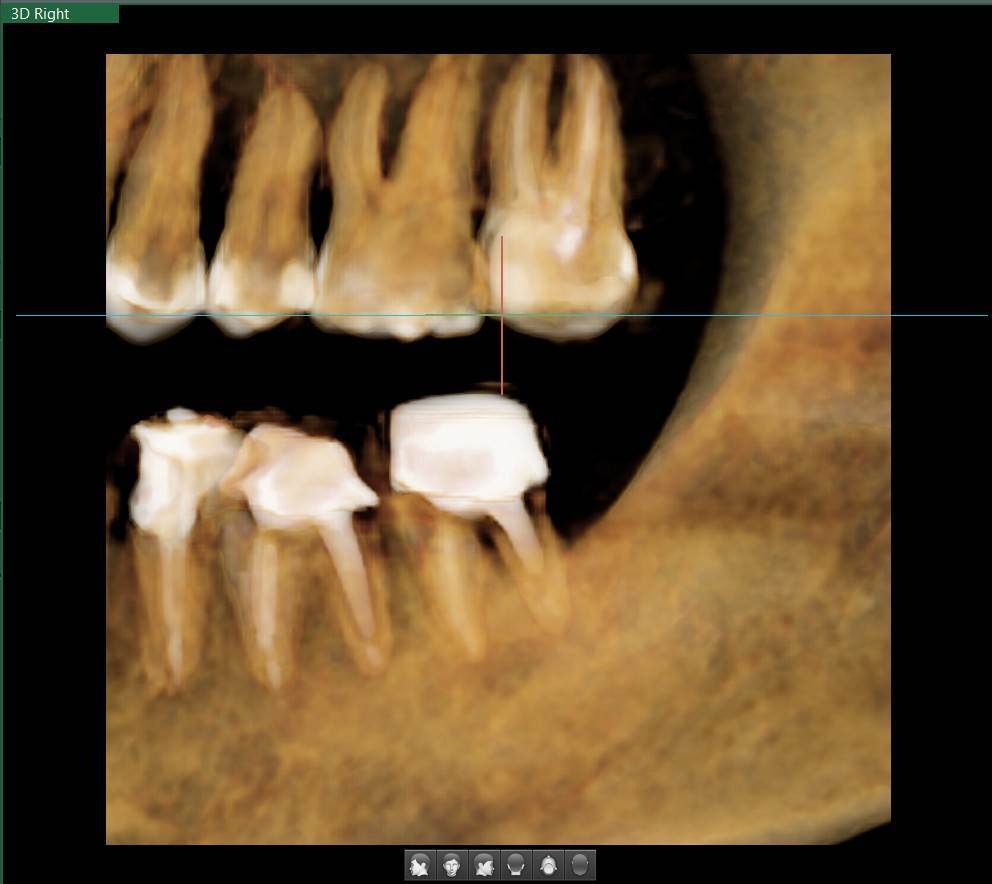

A-V-S Опубликовано 3 марта Поделиться Опубликовано 3 марта Здравствуйте. У меня такая ситуация: В начале января 2026 начал болеть зуб 7ка снизу слева - боль развивалась постепенно - в итоге стало больно жевать. Сделал КТ. Лечащий стоматолог сказал, что это проснулось спящее воспаление, перелечивать каналы зуба сложно - надо сверлить буром и доставать стекловолоконный штифт - надо удалять. В следующие дни открылся свищ и боль ушла. Свищ продолжает быть с периодическим набуханием и сдуванием после выброса гноя белого цвета. Этот зуб лечили с установкой стекловолоконного штифта чуть больше 5 лет назад. Посмотрите, пожалуйста, приложенные снимки и посоветуйте как быть - можно ли перелечить и сохранить зуб ? Ссылка на комментарий

АнтонТЛТ Опубликовано 3 марта Поделиться Опубликовано 3 марта Добрый вечер, лучше выложить несколько срезов этого зуба, либо архив с кт. По представленным снимкам, есть подозрение о наличии трещины между корнями зуба. 1 1 Ссылка на комментарий

Гарриевич Опубликовано 6 марта Поделиться Опубликовано 6 марта Не знаю обрадует Вас это или огорчит, но зуб можно сохранить соседний тоже с воспалением кстати 1 1 Ссылка на комментарий

red_butler Опубликовано 9 марта Поделиться Опубликовано 9 марта В 03.03.2026 в 22:49, A-V-S сказал: можно ли перелечить и сохранить зуб ? можно Ссылка на комментарий

Doc Опубликовано 10 марта Поделиться Опубликовано 10 марта 16 часов назад, A-V-S сказал: на соседнем свища нет. Тоже надо перелечивать вместе с 7 ? Отсутствие свища не снимает проблемы наличия кисты на этом зубе. Рано или поздно будет вам свищ, либо зуб так заболит, что придется удалять безо всякого свища. 1 Ссылка на комментарий